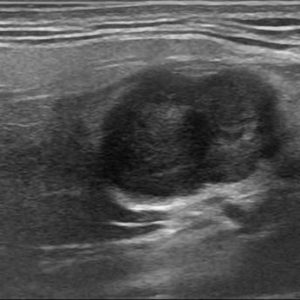

U tuyến nước bọt

Lượt xem: 170» 17-01-2021 -

U tuyến nước bọt

Lượt xem: 174» 17-01-2021 -

U tuyến nước bọt

Lượt xem: 149» 17-01-2021 -

U tuyến nước bọt

Lượt xem: 147» 17-01-2021 -

U tuyến nước bọt

Lượt xem: 146» 17-01-2021 -

U tuyến nước bọt

Lượt xem: 151» 17-01-2021 -

U tuyến nước bọt

Lượt xem: 146» 17-01-2021 -

U tuyến nước bọt

Lượt xem: 136» 17-01-2021 -

U tuyến nước bọt

Lượt xem: 132» 17-01-2021 -

U tuyến nước bọt

Lượt xem: 209» 17-01-2021 -

U tuyến nước bọt

Lượt xem: 150» 17-01-2021 -

U tuyến nước bọt

Lượt xem: 185» 17-01-2021 -

U tuyến nước bọt

Lượt xem: 151» 17-01-2021 -

U tuyến nước bọt

Lượt xem: 212» 17-01-2021 -